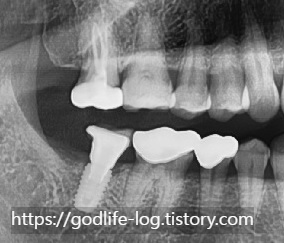

그냥 치아가 정출 된 상태로 임플란트를 하면 안 되나요?라고 궁금해하실 수 있는데요, 우리 입안은 공간이 한정되어 있습니다.

이렇게 한정된 구강 내에서 치아가 정출 된 상태로 임플란트 보철물을 제작하게 된다면 보철물 크기가 굉장히 작아질 수밖에 없습니다. 그렇게 되면 옆치아랑 높이가 맞지 않아서 음식물이 잘 낄 수도 있고 치아가 작아지면 유지력도 낮아지기 때문에 보철물 탈락 빈도수가 높아집니다.

이를 방지하기 위해서 대합 되는 치아의 일부를 삭제한다거나 삭제량이 많아질 경우 인위적으로 신경치료 후 크라운 치료를 동반해야 할 수도 있습니다.